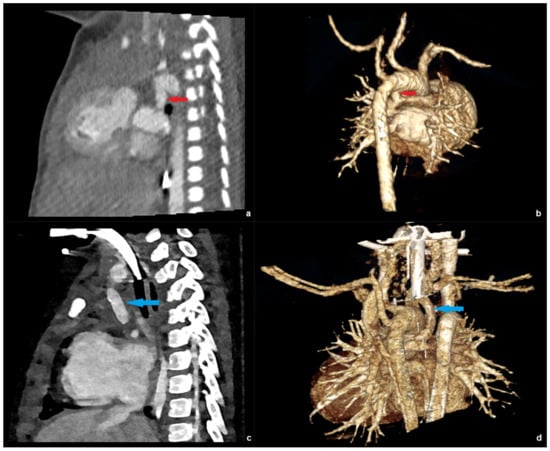

Figure 5.

EID-CT images of a patient with hypoplastic left ventricle and pulmonary atresia at the age of 10 days: sagittal (a) and 3D right posterior oblique (b) reconstruction depicting the patent ductus arteriosus (red arrow). PC-CT images of the same patient at the age of 17 month sharply depicting a Blalock-Taussig shunt (blue arrow) in the sagittal (c) and 3D right posterior oblique (d) view.